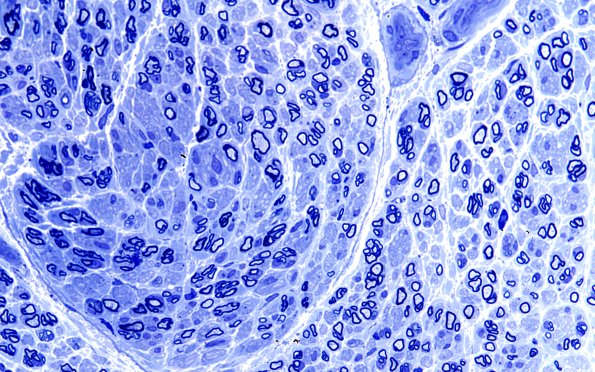

Washington University Experience | PERIPHERAL NEUROPATHY | 5 AXONAL REGENERATION | 13A4 (Case 13) Plastic 60X 1

13A4,5 Two things become apparent with increasing magnification: 1) there are numerous regenerative clusters and 2) the axons that remain show thinned-myelin-for-axon-caliber, evidence of a cycle of degeneration and regeneration. (Plastic sections)